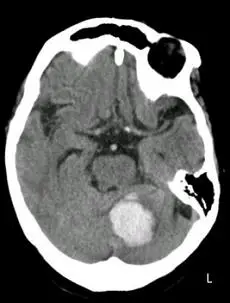

一位出血性中風病患入院後的影像檢查如下圖,該病患最不可能出現下列何項臨床檢查結果?

- 影像類型:腦部電腦斷層掃描(Brain CT),無顯影劑(Non-contrast)。

- 病灶位置:

- 在後顱窩(Posterior fossa)可見一團高密度(Hyperdense,白色)的區域,這是典型的急性出血訊號。

- 根據影像右下角的「L」標記(代表病患左側),以及CT慣例(影像右側為病患左側),該出血病灶位於左側小腦半球。

- 病灶周圍有些微低密度的水腫區域,且可能對第四腦室造成壓迫。

- 診斷:左側小腦出血(Left Cerebellar Hemorrhage)。